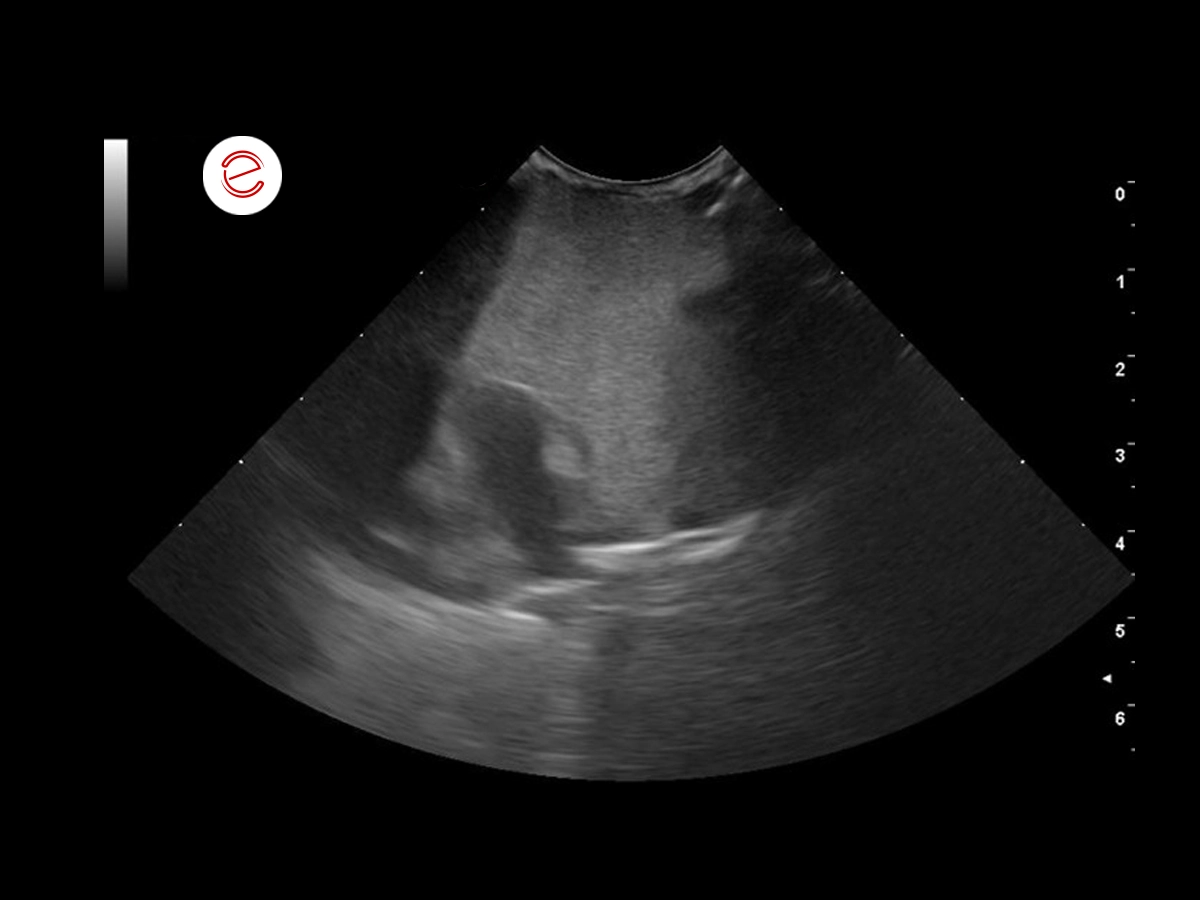

After 2 months of treatment, the bird showed improvement clinically and in the ultrasound examination the mass/granuloma has visibly reduced in size.

The yellow arrow shows the scar tissue that is now present.